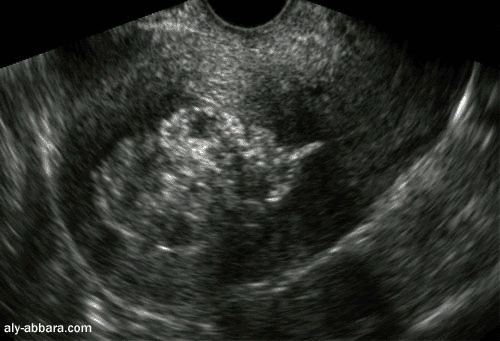

Rétension trophoblastique dans l'utérus

ou polype placentaire

Cette image de 58 x 37 mm, hétéro-échogène qui occupe la totalité de la cavité

utérine, elle a été mise en évidence deux mois après un accouchement naturel